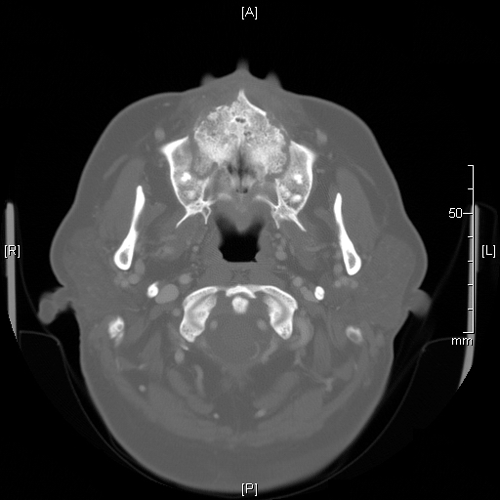

Image of the Case: CT scan, coronal view, of the sinuses reveals an opacified left ostiomeatal unit on the left and thickening of the mucosa on the right (Panel A). CT scan, axial view. The hard palate and maxilla show destructive changes and fractures causing a “moth-eaten” appearance (Panel B).